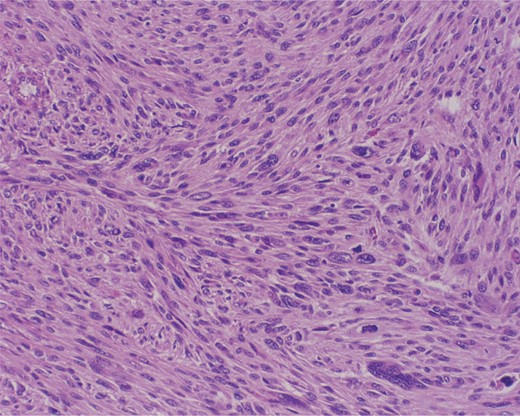

The excisional biopsy was performed in June 2012, which revealed a diagnosis of leiomyosarcoma (slides seen in Figs. 3–5).

Cross section at low power. Intersecting bundles. Multinucleated giant cell in the bottom right.